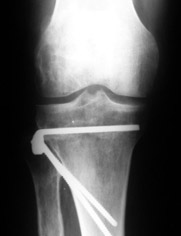

Большая просьба прокомментировать прилагавшиеся снимки. Видно, что сделано что-то красивое, но не совсем понятно, по какому поводу, как рассчитывалась коррекция, и что именно сделано.

Поводом для проведения всех корригирующих остеотомий у исследуемых пациентов служил гонартроз 1-3 стадии, косметическая коррекция в большинстве случаев являлась вторичной.

Хотя любого больного она не в меньшей степени интересовала. При всех видах остеотомий обязательным требованием являлась восстановление баланса пассивных и динамических сил путем восстановления оси конечности, стабильности связочного аппарата и контроля над мышечной активностью при осевой нагрузке. Как правило, учитывалась сохранность гиалинового хряща на компенсирующем нагрузку мыщелке бедра или большеберцовой кости. Предоперационное планирование осуществляли с поднагрузочных рентгенограмм обоих конечностей.

Дополнительными методами диагностики являлось измерение внутрикостного давления в зоне гипернагрузки и радионуклидные исследования нуклидами технеция. Применялись различные варианты остеотомий на различных сегментах. Для коррекции варусной-торсионной деформации:

высокие плюс, минус остеотомии большеберцовой кости,косая остеотомия малоберцовой. Для коррекции вальгусной деформации применялась плюс, минус надмыщелковая остеотомия бедренной кости. Фиксацию при высокой подмыщелковой остеотомии производили уникальной клинковой пластиной и тяговыми кортикальными винтами. Угол коррекции выставлялся

специальным угломером и направителем.